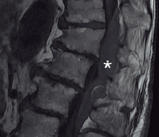

La combinación de anestesia general con analgesia epidural se considera como el gold-estándar para la cirugía abdominal por vía laparotómica. Ante la aparición de síntomas neurológicos en el postoperatorio inmediato de pacientes portadores de catéter epidural es preciso sospechar de complicaciones relacionadas con el mismo.En caso de presentar un hematoma epidural, es fundamental un diagnóstico precoz con prueba de imagen y la realización de una cirugía descompresiva urgente.